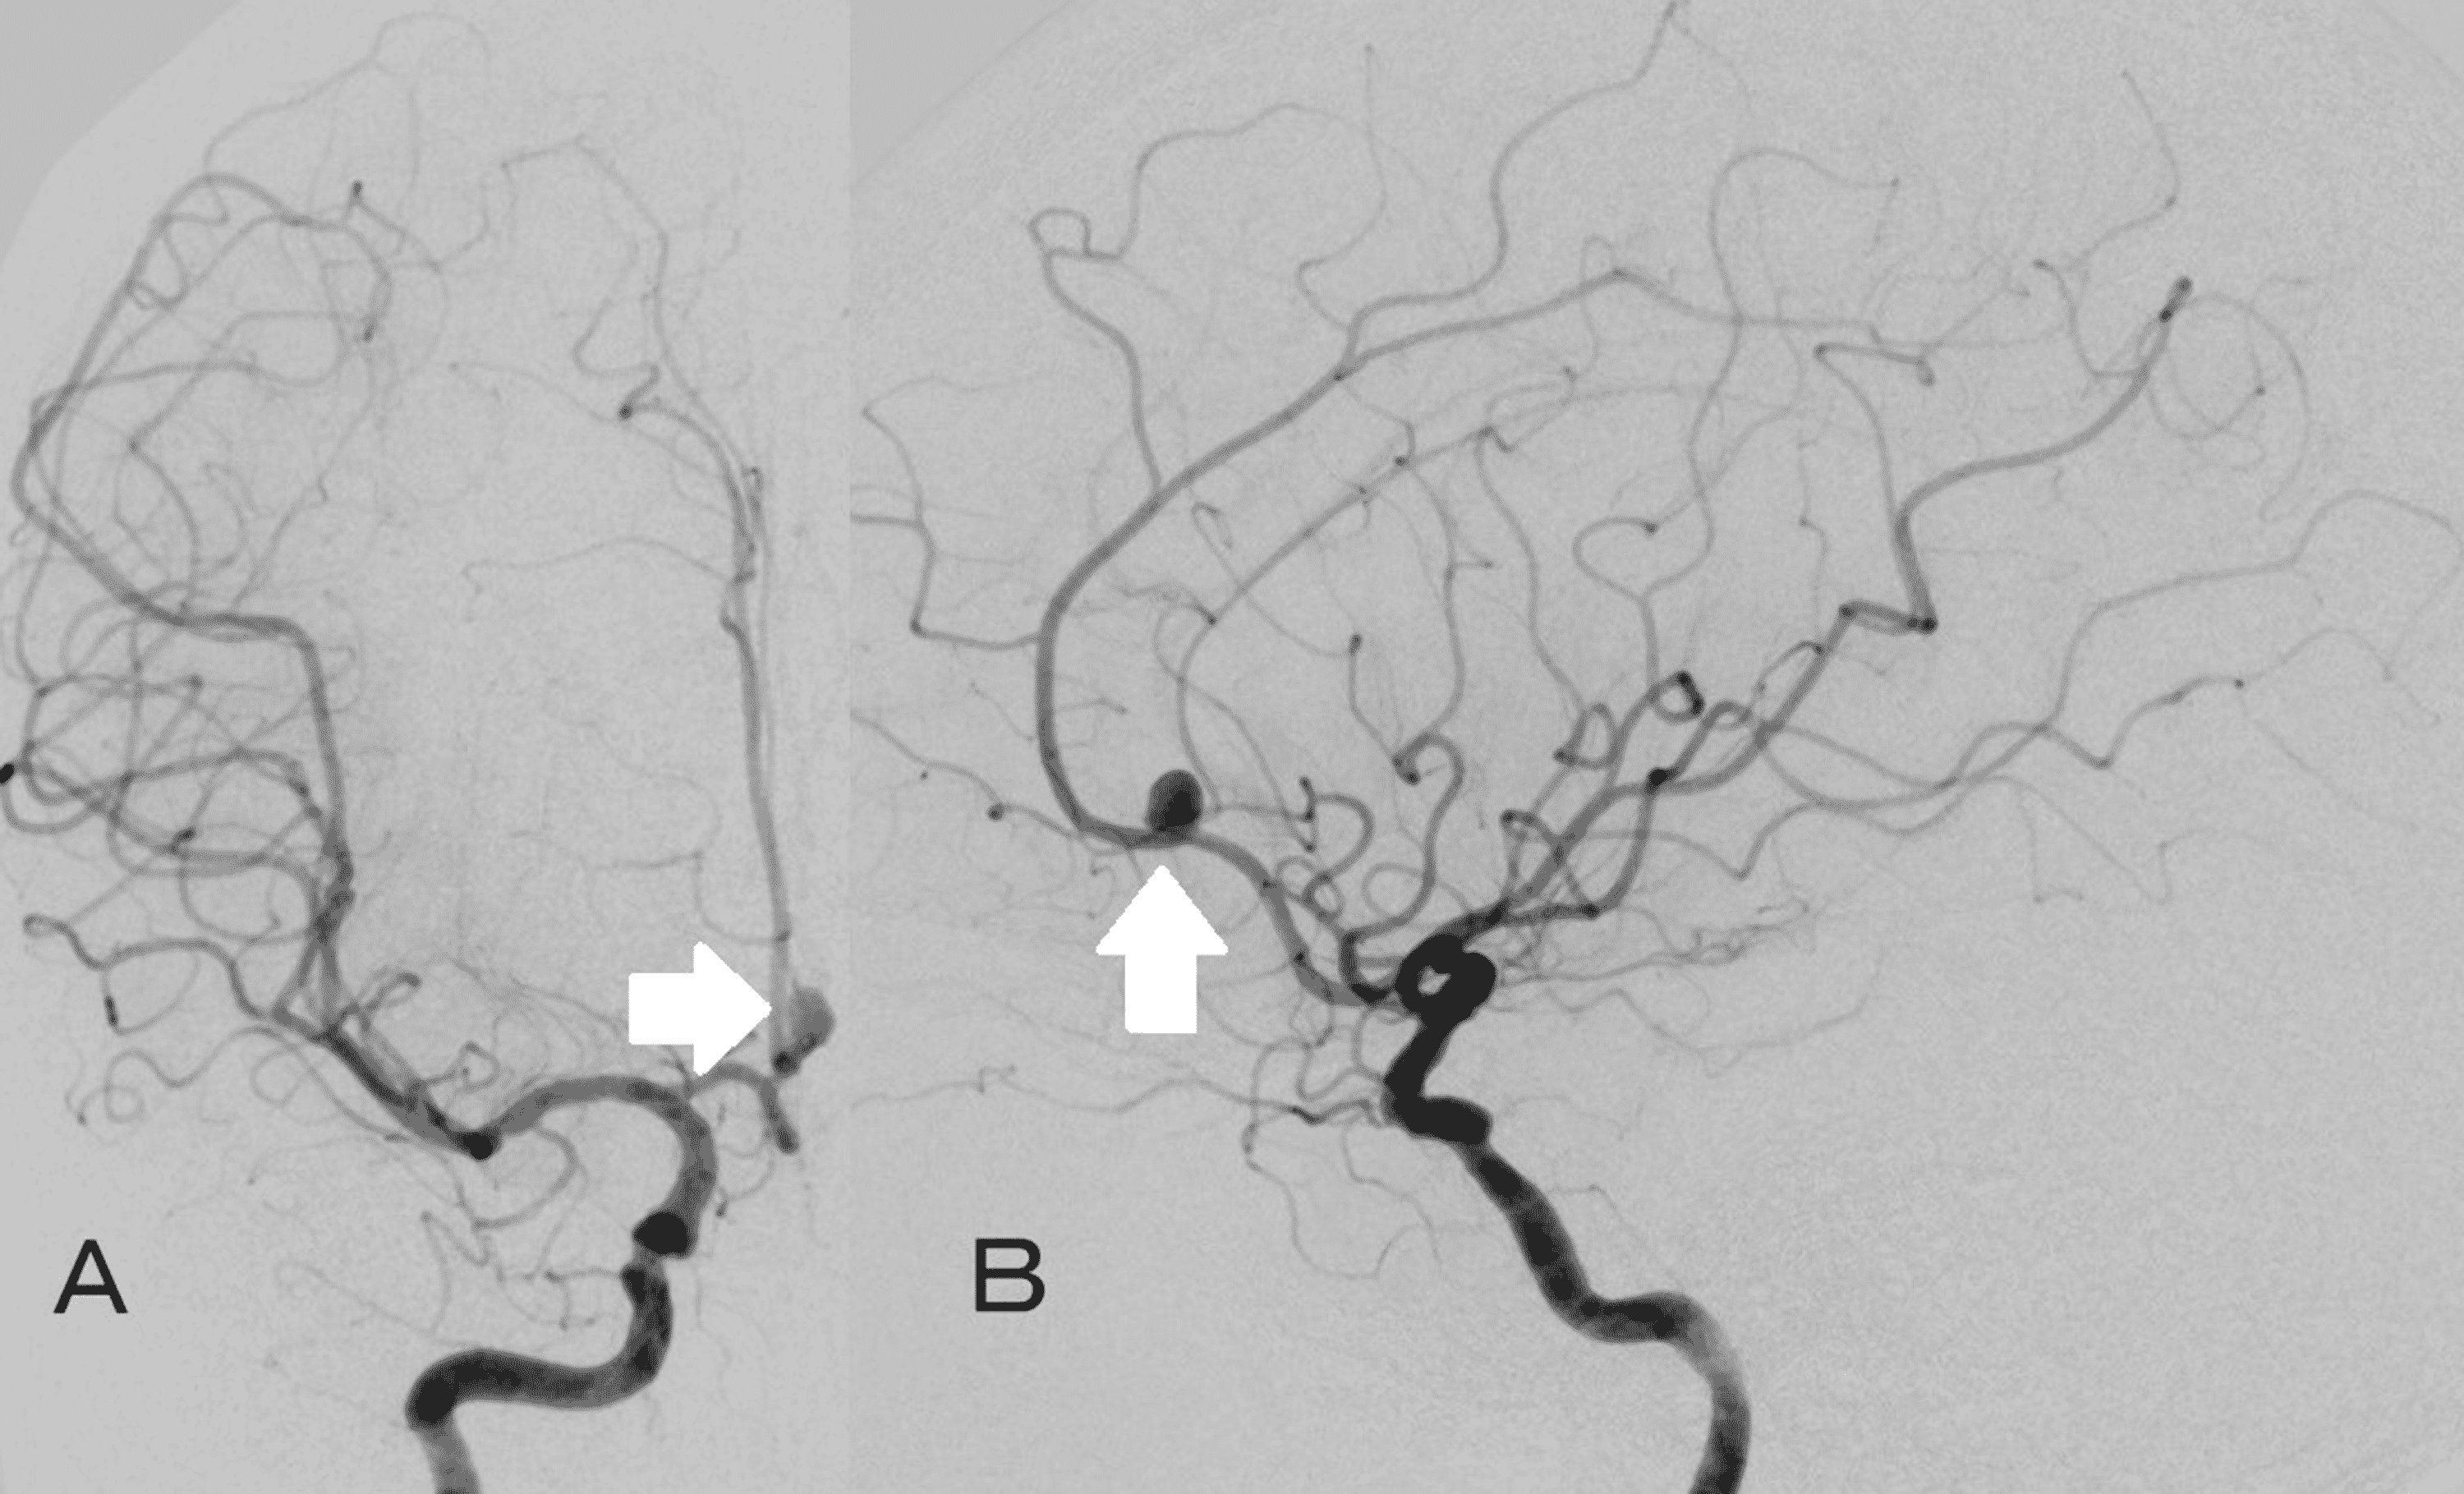

From www.strokejournal.org

Coil Embolization through Collateral Pathway for Ruptured Vertebral Coil Embolization Dissecting Aneurysm Effective treatment strategies for vertebrobasilar dissecting aneurysms (vbdas) remain controversial due to their high morbidity. Stent implantation with or without coiling was performed in patients with. Intracranial dissecting aneurysm (ida) refers to the pathological dissection between the intima and media or between the. Endovascular coil embolization is a percutaneous approach to treat an intracranial aneurysm from within the blood vessel. Coil Embolization Dissecting Aneurysm.